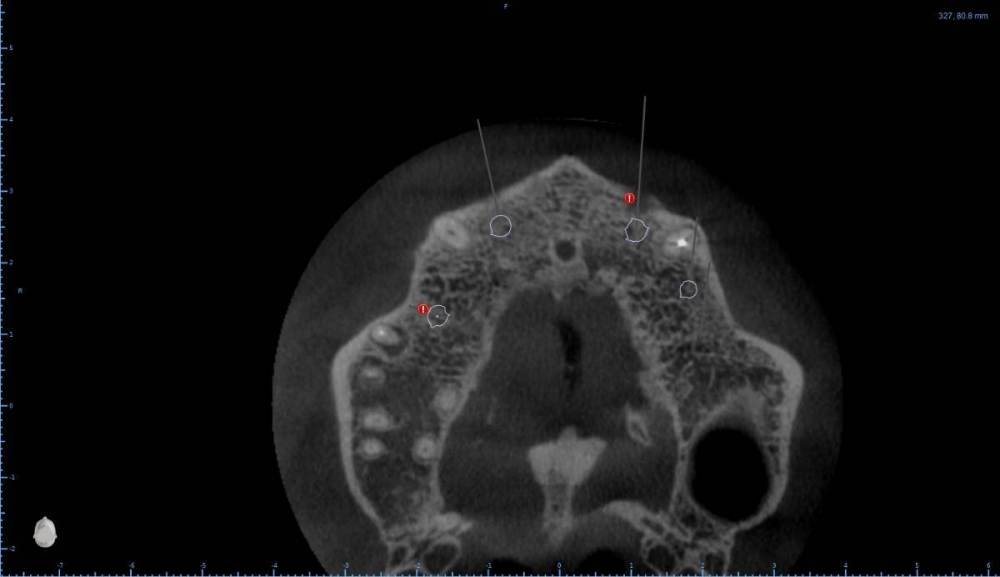

Женька Опубликовано 6 августа, 2022 Поделиться Опубликовано 6 августа, 2022 В общем планируется большая (по крайней мере для меня) работа. Вот такой товарищ у нас. Делали бы НКР в области 2.5з? или поставили бы чисто по кости, а оголённый участок закрыли присыпкой и мембраной? Также вопросы по двойкам имеются. Бугор есть, сразу оговорюсь, правда только с одной стороны. Также не понятно пока "как его правильно готовить" этот бугор, чтобы закрыть такие дефекты вестибулярной пластинки. Скрины постарался нарезать по максимуму. Там ещё будет ортодонтия конечно же. Интрузии, движения всякие и тд) Да, знаю, что планировать без цифрового гипса неправильно, но что имею. Ссылка на комментарий

Irouil Опубликовано 6 августа, 2022 Поделиться Опубликовано 6 августа, 2022 Если будет ортодонтия, то не проще ли вытянуть двойки чтобы вырастить ткани? ИДР тут нужен основательный очень, винты придётся крутить тоже очень длинные В области премоляра не вижу смысла что-то графтить, если хочется чего-то натолкать - можно стружки со сверла упаковать в дефект, но имхо не обязательно. А если сместить винт небно и чуть аннулировать, преп только пилотным и дальше конденсировать... ну Вы поняли 1 Ссылка на комментарий